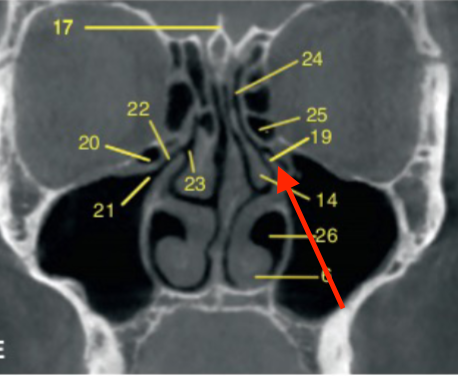

middle turbinates/concha

identify the structure

inferior nasal meatus

identify structure

nasal septum

nasolacrimal duct

maxillary sinus

what is indicated by the GREEN dot

ostium (of maxillary sinus)

uncinate process

sphenoid sinus

frontal sinus

ethmoid air cells

identify the structures

orbit

infraorbital foramen